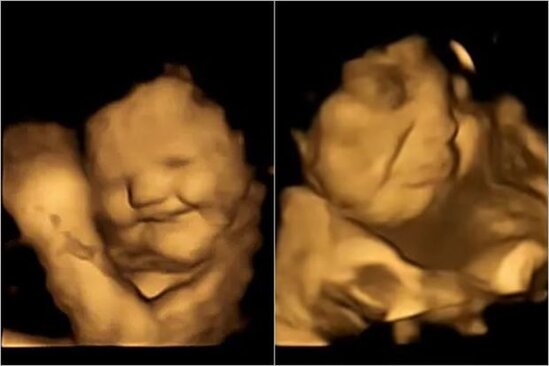

Bu barədə Durham Universitetinin tədqiqatçıları maraqlı tədqiqat aparıblar. Onlar 18-40 yaş arası 100 hamilə qadının 4D ultrasəs müayinəsini aparıblar və ana bətnindəki körpələrin analarının yediyi qidaların dadına necə reaksiya verdiyinə baxıblar.

Qadınlara hər skandan 20 dəqiqə əvvəl 400 mq yerkökü və ya 400 mq brokkoli tozu olan kapsul verilib, bundan sonra başqa qidalar və ya ətirli içkilər istehlak etməmələri xahiş edilib. Bəzi hamilələr isə ümumiyyətlə heç nə qəbul etməyiblər.

Nəticələr göstərib ki, hətta az miqdarda yerkökü və ya kələm dadlandırıcısı döldə reaksiyaya səbəb olmaq üçün kifayətdir.

Qadınlar yerkökü yeyəndə bətnlərindəki körpələr gülümsəməyə meylli olublar, lakin kələm kapsulunu yeyəndə üz-gözlərini turşudublar.

"Skaner zamanı doğulmamış uşaqların kələm və ya yerkökü dadına reaksiyasını izləmək və bu anları valideynləri ilə bölüşmək həqiqətən heyrətamiz idi", - deyə tədqiqatın aparıcı müəllifi Beyza Üstün bildirib.